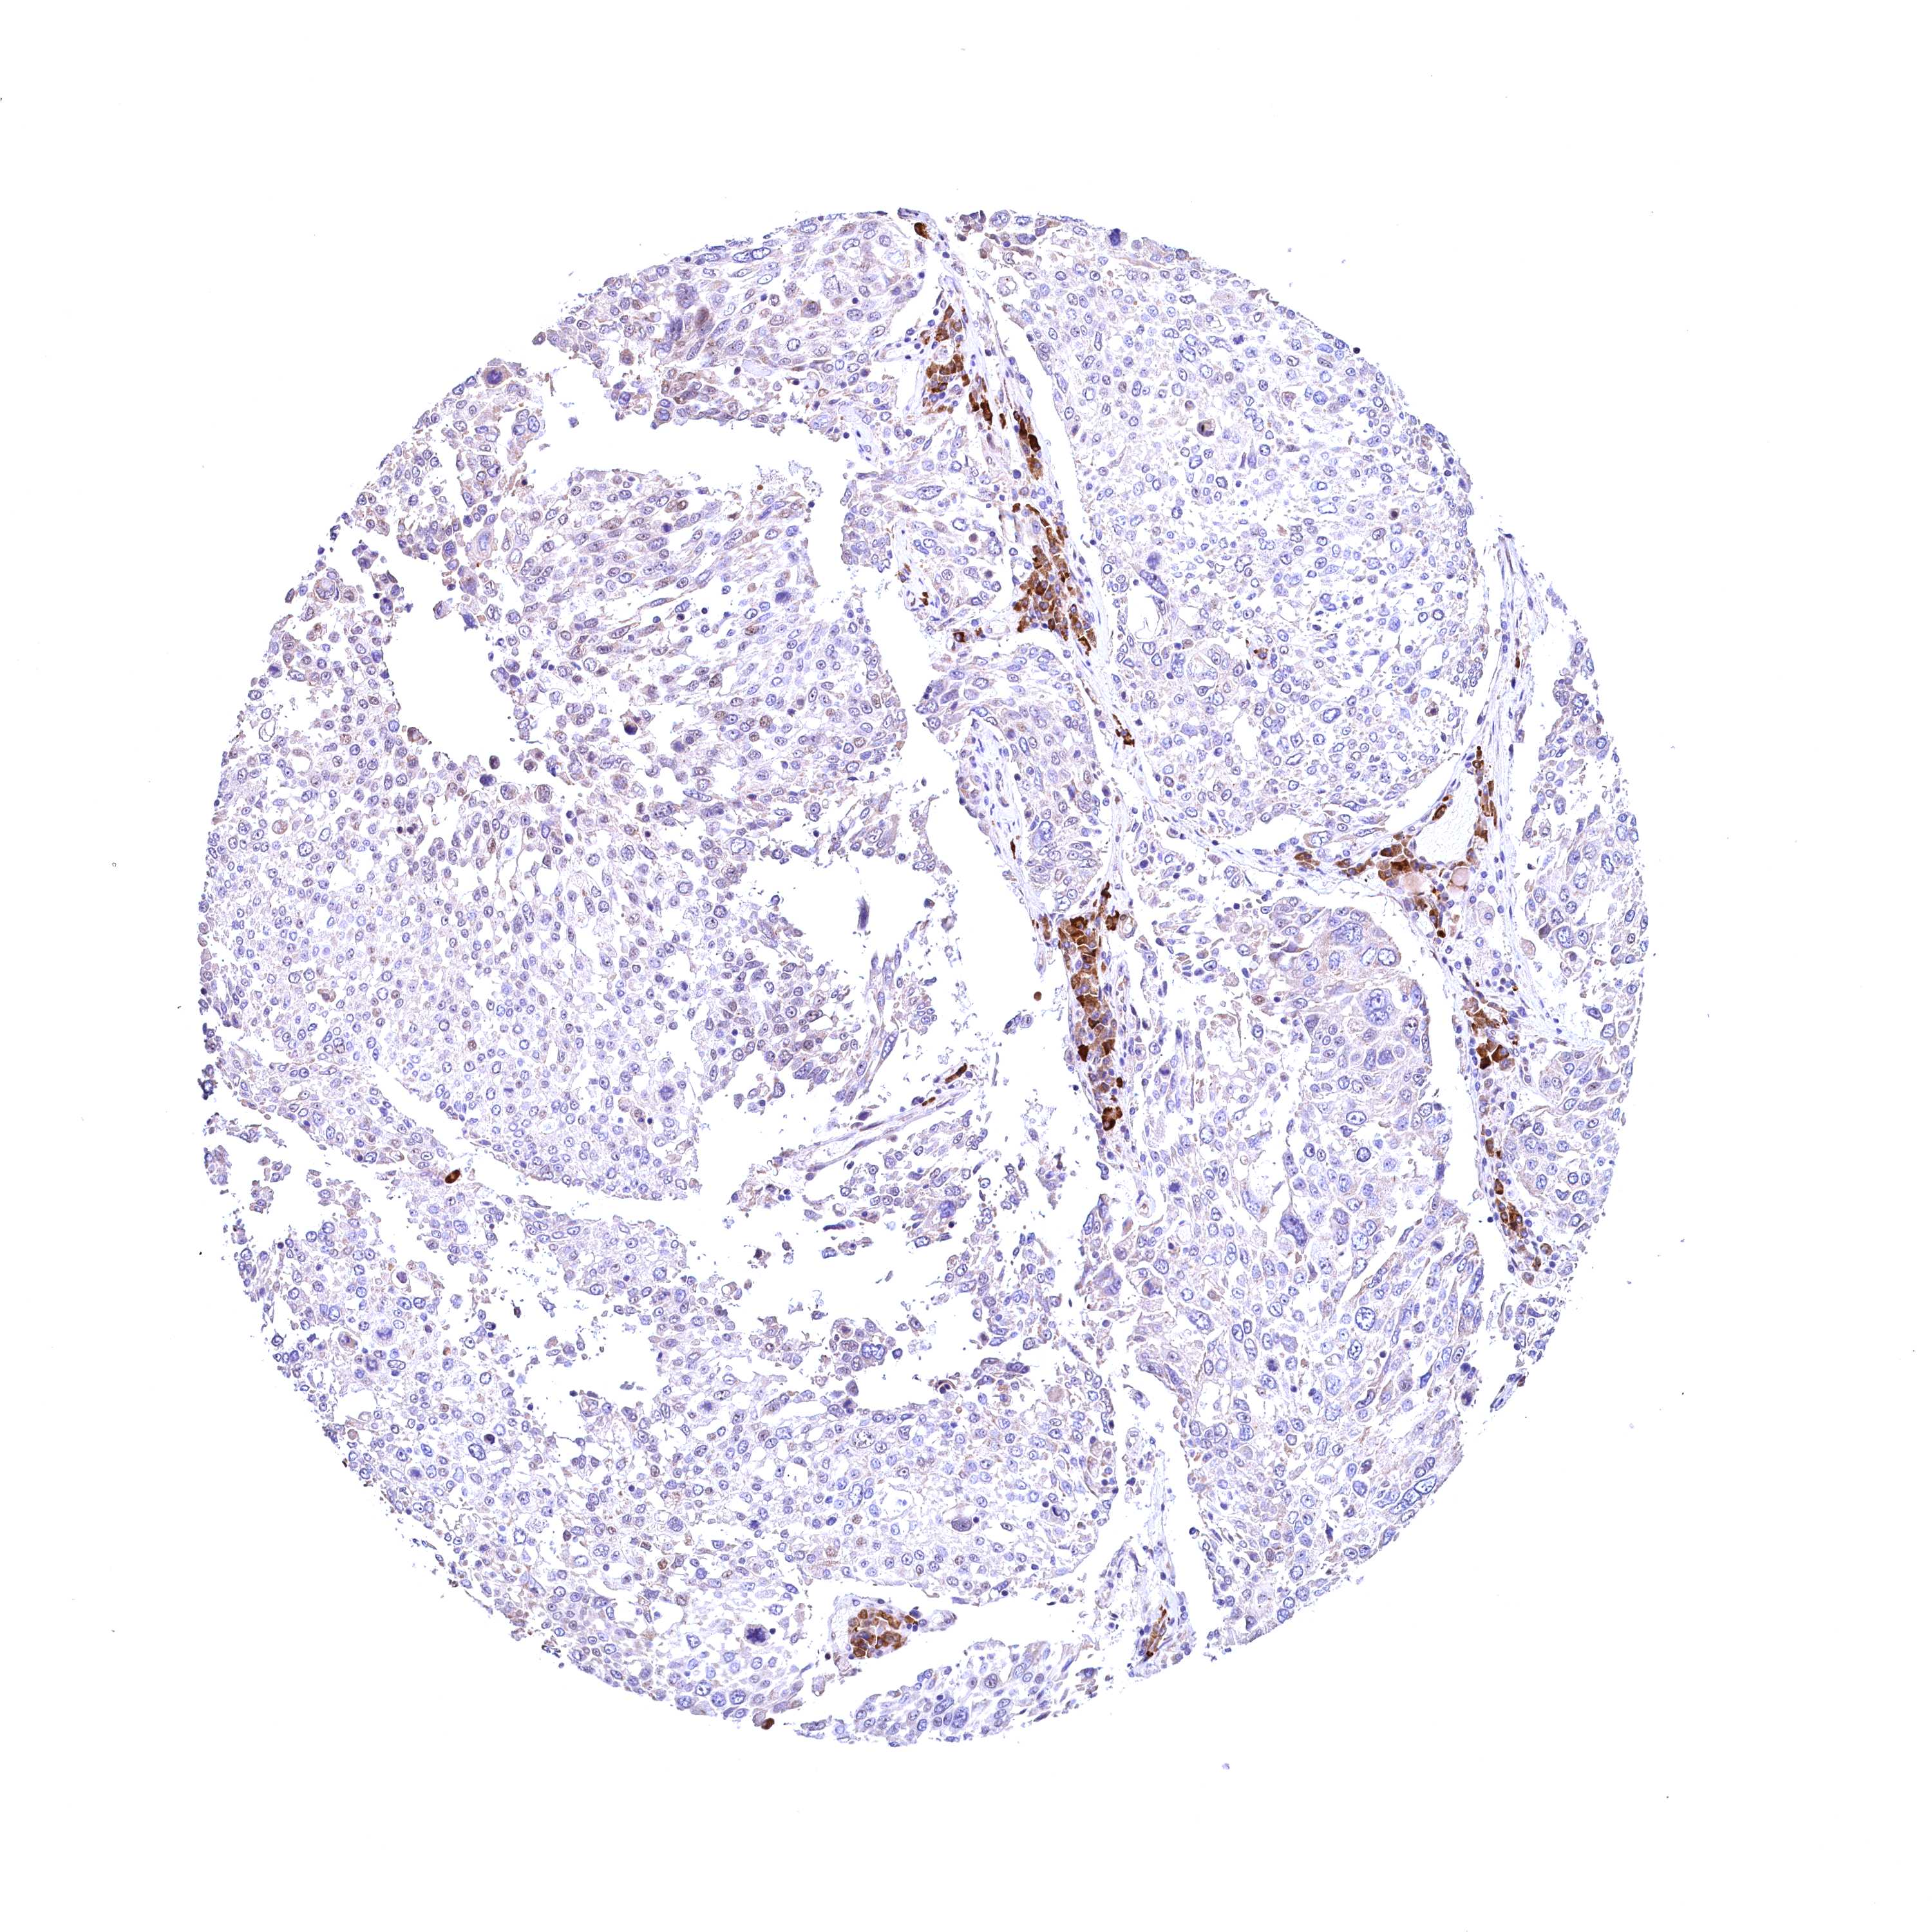

CANCER LUNG CANCER Show tissue menu

LUAD TCGA LUAD VALIDATION LUSC TCGA LUSC VALIDATION PROTEIN LUAD CPTAC PROTEIN LUSC CPTAC PROTEIN EXPRESSION

ANTIBODIES

AND

VALIDATION